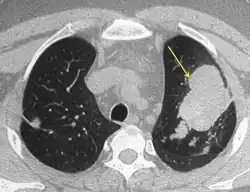

CT of the chest showing high attenuation mucous (HAM) impaction (yellow arrow). This is considered pathognomic for allergic bronchopulmonary aspergillosis (ABPA).

Mucoid impaction of the upper and lower airways is a common finding.[7] Plugs are hypodense but appear on CT with high attenuation (over 70 Hounsfield units[31]) in up to 20% of patients. Where present it is a strong diagnostic factor of ABPA and distinguishes symptoms from other causes of bronchiectasis.[13]

CT scans may more rarely reveal mosaic-appearance attenuation, centrilobular lung nodules, tree-in-bud opacities and pleuropulmonary fibrosis (a finding consistent with CPA, a disease with ABPA as a known precursor).[7] Rarely other manifestations can be seen on CT scans, including military nodular opacities, perihilar opacities (that mimic hilar lymphadenopathy), pleural effusions and pulmonary masses. Cavitation and aspergilloma are rarer findings, not exceeding 20% of patients, and likely represent a shift from ABPA to CPA if accompanied by pleural thickening or fibrocavitary disease.[13]